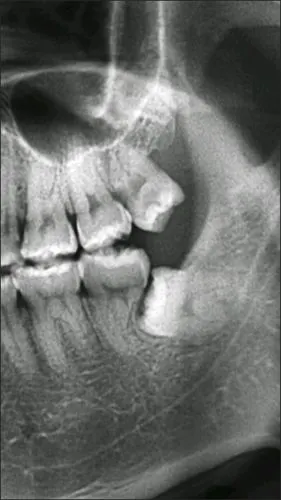

在我们口腔医学上专业的称之为-----第三磨牙,请看下图:下颌阻生智齿

右下第二磨牙

水平低位埋伏下颌第二磨牙的正畸牵引治疗:附1例报告

下颌第二磨牙c3型弯曲根管一例